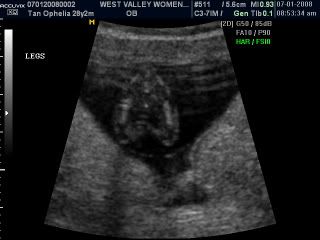

When she was scanning baby legs she asked, would you like to know the gender of the baby, I look and hubby and was like! Yes of course!!! We were really surprised! Cause many mummies can only see their baby's gender at about 4 and a half months! We were like really you can see that already?! And she nods her head...

And the she pointed to us the little pokey thing! Our darling baby is a BOY!!! OMG... Tears started streaming down my face, I didn't know why. I guess its all the excitement and the confirmation of the little life inside me? Life is such a miracle! I mean I told Jason during the first few weeks that I think we are having a boy and OMG its really a boy!!! Jason teared too but wasn't as dramatic as me where I required tissue to wipe all those teardrops off!!!

Anyway our darling boy, i think we shall re nick name you as our little beanie instead, thumbelina is just too girly for you! Here are pictures from the scan! And my little paunch at 12 weeks. Suyi says that I must show them pictures of my paunch!!! Haha... And so here it is!